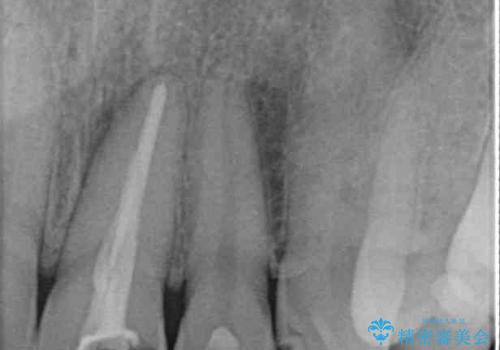

むし歯で神経が取り除かれており、歯の変色と充填材の変色などにより、つぎはぎのような前歯となっていました。

膿の出口も認められたため、まずは根管治療を実施し、オールセラミッククラウンにて補綴治療を行うこととしました。